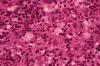

The overall pathology is that of a granulomatous inflammation with acute and

chronic inflammatory cell infiltration as illustrated in

D. Yeast form microorganisms with thick

refractile walls are present as illustrated in

The

organisms can be easily found on hematoxylin-eosin stained sections.

They occur as yeast of

10-25

mm in

diameter. The centrally located fungal cell cytoplasm is basophilic to

amphophilic and is 8-15 mm in diameter (so-called “basophilic body”); the

cell wall is thick, refractile and poorly stained. Single broad based budding is

a typical feature. It must be distinguished from the multiple buds that are seen

in Paracoccidodes brasiliensis (South American form of blastomycosis).